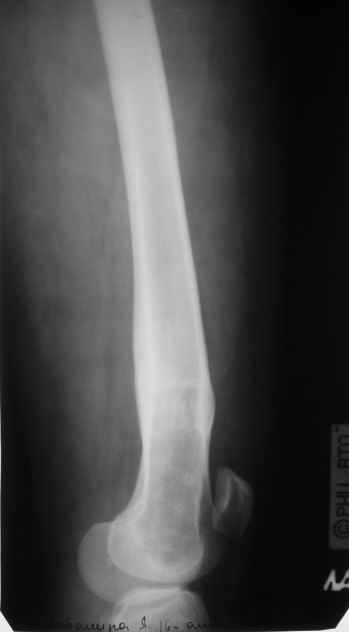

Перелом проксимального отдела диспластичного бедра

Пациентка 23 лет, доставлена в клинику с Диагнозом: Закрытый сегментарный оскольчатый перелом левой бедренной кости в верхней и средней трети. Травма в результате ДТП 10.03.2006г. Из анамнеза у пациентки диспластический левосторонний коксартроз, S-образный сколиоз 2ст. В 1999г в Кургане выполнялась остеотомия бедра в нижней трети и коррекция укорочения конечности на 3 см (рентгенограммы бедра и таза до травмы в приложении). До получения травмы пациентка ходила без боли с полной нагрузкой на левую ногу. Учитывая дисплазию левого ТБС, пациентке, вероятно, предстоит операция тотального эндопротезирования лев ТБС, что требует анатомичного восстановления проксимального отдела бедра.

Рассматриваются следующие вариант остеосинтеза: 1) Экстракортикальный остеосинтез проксимального и дистального перелома пластиной с угловой стабильностью типа LISS( г Рыбинск);

2) Ретроградный интрамедуллярный блокированный остеосинтез дистального перелома и накостный синтез проксимального пластиной с угловой стабильностью;

3) Остеосинтез бедра в аппарате внешней фиксации с фиксацией таза и возможной открытой адаптацией фрагментов.